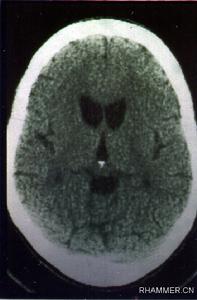

該病以運動障礙、痴呆和精神行為異常為主要臨床表現。90%的亨廷頓病患者中,舞蹈樣動作是最常見的運動障礙。舞蹈動作常自肢體遠端開始,病情進展時逐漸發展為全身性並影響隨意運動。其病理改變包括神經元缺失和神經膠質增生,主要見於大腦皮質和紋狀體。